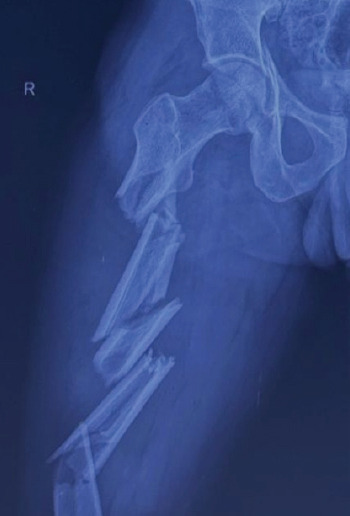

Case report: A 34-year-old male presented with multiple fractures, including a triple-segmental shaft femur fracture, following a high-energy road traffic accident. An intramedullary nail was used for closed reduction and internal fixation of the femur fracture, which provided stable fixation while preserving the blood supply and minimising soft-tissue damage.